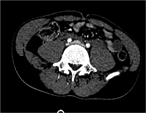

Conservative management of a traumatic common iliac venous pseudoaneurysm: a case report

Walker Lyons and others

Journal of Surgical Case Reports, Volume 2017, Issue 5, May 2017, rjx085, https://doi.org/10.1093/jscr/rjx085